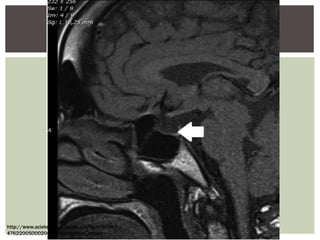

Síndrome de Sheehan en

una mujer de 37 años de

edad que presentó con una

historia clásica de

hipopituitarismo de 3 meses

de evolución luego de un

parto complicado. La

imagen de una MRI T1, un

corte Sagital, muestra un

silla turca vacía con

herniación del quiasmo

óptico (flecha) en la silla

turca.

La imagen característica esla de "silla turca vacía", la cual aparece varios meses posteriores al evento hemorrágico. Síndrome de Sheehan en una mujer de 37 años de edad que presentó con una historia clásica de hipopituitarismo de 3 meses de evolución luego de un parto complicado. La imagen de una MRI T1, un corte Sagital, muestra un silla turca vacía con herniación del quiasmo óptico (flecha) en la silla turca.